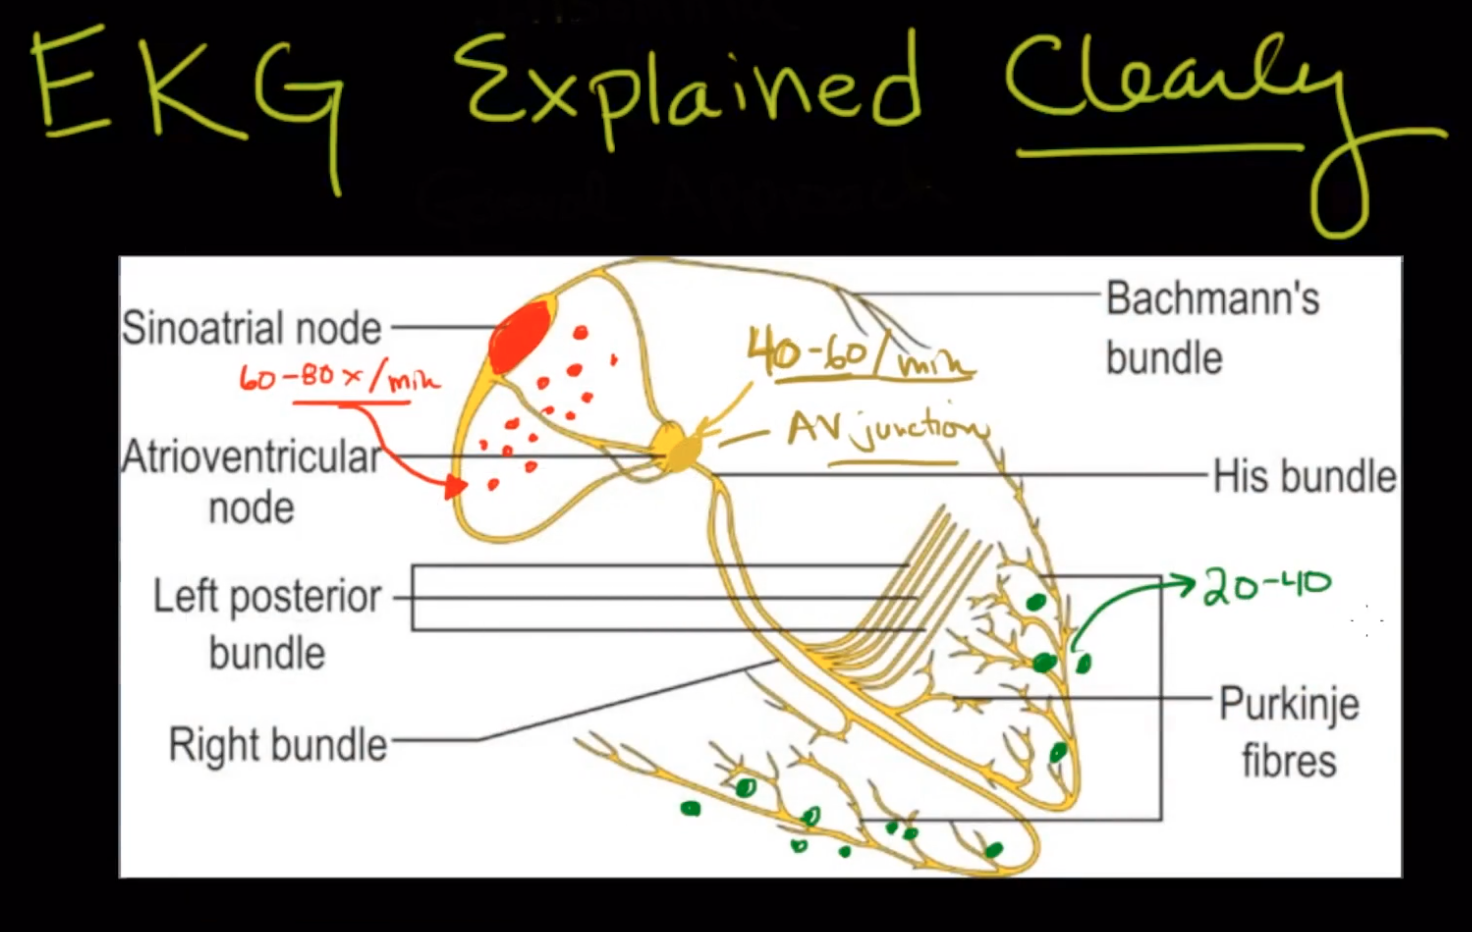

“The Staff of Professors of the Royal Caroline Institute has on 23rd October, 1924, decided to confer this year’s Nobel Prize in Physiology or Medicine to the Professor of Physiology at the University of Leiden, Willem Einthoven, for his discovery of the mechanism of the electrocardiogram.

“Einthoven’s name is linked partly with the design of a physical instrument, the string galvanometer, partly with the so-called electrocardiogram, a record of the electrical potential fluctuations at the surface of the body, which accompany the heart beat. The heart beat, like the piston movement of a steam engine, is a cyclic process. Behind this process lies, in the first place, a similarly cyclic process in the heart muscle.

…

“The same mechanism governing the characteristics of the electrocardiogram, also governs the characteristics of the mechanical process during the heart beat. We should remember in this connection that the mechanical process not only consists of the succession of the stimulation of the separate parts of the heart compartments, but also of the cooperation of the individual parts of the heart wall which form the essential condition for the mechanical effect in the individual ventricle or in the individual auricle. A deficiency in this cooperation can, with regard to the mechanical effect, be as fatal as a valvular insufficiency. Today, the importance of the mechanism discovered by Einthoven can easily be realized.”